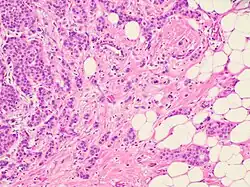

Histopathology of invasive carcinoma of no special type, H&E stain, intermediate magnification. It shows typical plump tumor nests (rather than the single-file linear pattern of invasive lobular carcinoma). The presence of tumor nests in adipose tissue at right in image strongly favors invasiveness.

High magnification of invasive carcinoma of no special type shows non-specific adenocarcinoma features.

On microscopic evaluation carcinomatous cells are seen below the basement membrane of lactiferous ducts and invade into the surrounding breast stroma. Otherwise, there are no specific histologic characteristics, essentially making it a diagnosis of exclusion.[21] The histopathologic characteristics seen in these lesions are heterogenous. The cells of a lesion of invasive carcinoma NST may retain >70% ductal differentiation or appear completely undifferentiated. The tumor cells may be arranged in sheets, nests, cords, or singly distributed. They are pleomorphic (i.e., vary in size and shape). They usually have prominent nucleoli and multiple mitotic cells per magnified field of view, which are features generally consistent with cancerous cells. The surrounding non-ductal tissue, known as stroma, can range from none to abundant.[22][23]